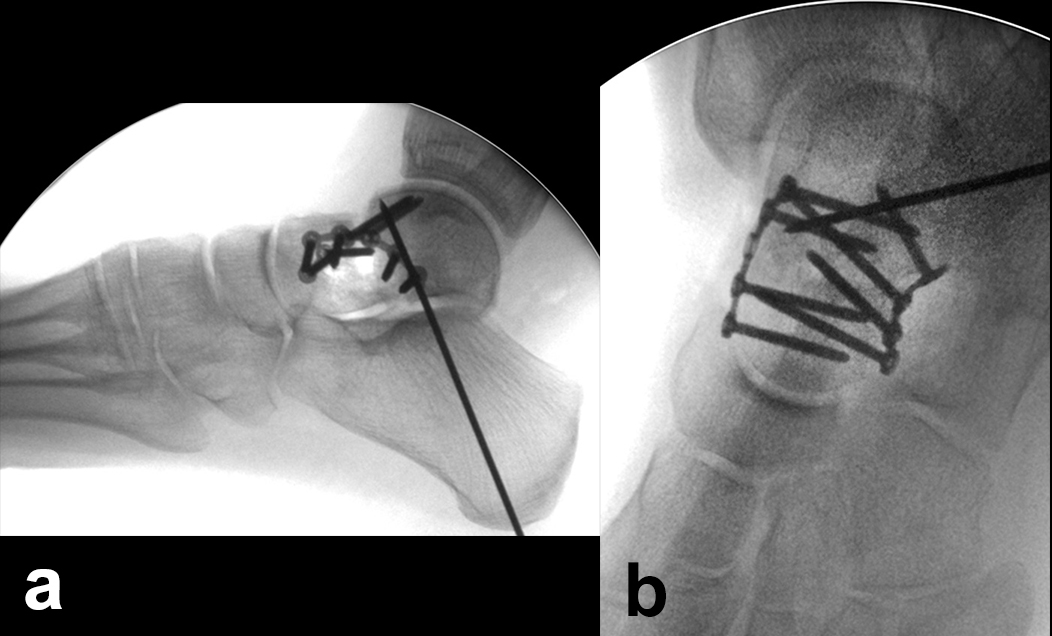

Talushalsfrakturen

Dislozierte Talushalsfrakturen werden zur anatomischen Reposition über einen anteromedialen und über einen zusätzlichen anterolateralen Zugang adressiert 244. Durch die bilaterale Kontrolle der Reposition können Rotations- oder Achsenfehlstellungen des Talus verhindert werden. Der anteromediale Zugang wird geschwungen vom Vorderrand des Innenknöchels bis zur Tuberositas ossis navicularis ausgeführt (Abb. 5). Der anterolaterale Zugang liegt zwischen Fibulaspitze und Proc. anterior calcanei. Im eigenen Vorgehen wird ein schräg verlaufender Zugang nach Ducroquet-Ollier vor dem Außenknöchel und entlang der natürlichen Hautfältelung bevorzugt 4 (Zwipp, Rammelt 2014). Der Zugang zum Proc. fibularis tali und lateralen Talushals erfolgt direkt über den Sinus tarsi.

Die Reposition des Talushalses erfolgt unter wechselseitiger Sicht von medial und lateral 24. Zur Manipulation können senkrecht zur Fraktur in die Hauptfragmente eingebrachte Kirschnerdrähte hilfreich sein 4. Nach temporärer Retention mit axial eingebrachten Kirschnerdrähten und visueller sowie Bildwandlerkontrolle werden zur Stabilisierung vorzugsweise Schrauben benutzt (Abb. 6). Müssen diese nahe zum Talonavicular-Gelenk eingebracht werden, sind Doppelgewindeschrauben oder die Verwendung einer Kopfraumfräse zum Versenken des Schraubenkopfes unter Knorpelniveau erforderlich. In jedem Fall sollte bei der Schraubenosteosynthese aufgrund der typischerweise vorliegenden medialen Trümmerzonen auf die Vermeidung von Zugkräften geachtet werden, um eine Verkürzung der medialen Seite des Talus mit nachfolgender Varusfehlstellung zu vermeiden 30. Kleinste, nicht refixierbare Fragmente werden verworfen, um freien Gelenkkörpern vorzubeugen. Auf der lateralen Seite hingegen liegt recht häufig eine einfache Fraktur vor, welche in einem Kortikalis-Sporn am Proc. fibularis tali ausläuft und sich für eine Zugschraubenosteosynthese eignet. Die Verwendung kanülierter Schrauben kann im Einzelfall hilfreich sein. Es ist jedoch darauf zu achten, dass es nach dem Überbohren des Führungsdrahtes nicht zu einer erneuten Dislokation der Fragmente kommt 24.

Verbleibt nach der Versorgung aller knöchernen Verletzungen eine ligamentäre Instabilität, so ist zur sicheren Bandheilung und damit auch Protektion der Osteosynthese eine temporäre Gelenktransfixierung für 6 Wochen indiziert 5. Dies betrifft nach der Versorgung von Talushals- und –korpusfrakturen eher das Subtalar-Gelenk (Abb. 10), nach Taluskopffrakturen eher das Chopart-Gelenk 12.